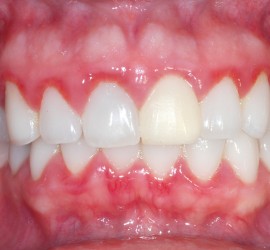

Аномалии строения и пороки развития зубов Пороки тканей зуба многообразны, они могут проявляться изолированно и сочетаться с аномалиями строения и пороками развития органов и систем всего детского организма, в том числе челюстно-лицевой области. Ткани зуба имеют эктодермальное (эмаль) и мезодермальное (дентин, пульпа, цемент) происхождение. В связи с этим пороки эмали […]